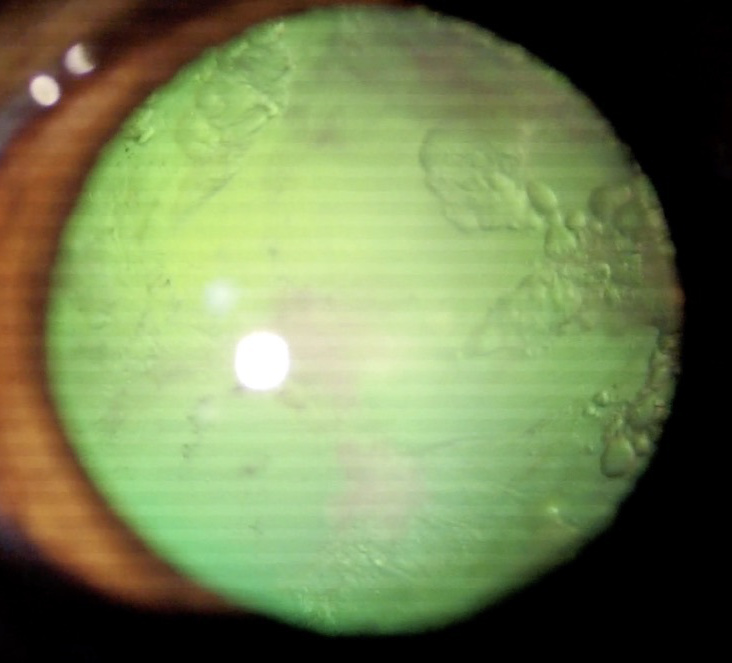

犬 白内障

白内障手術前

犬 網膜剥離

白内障手術1ヶ月後